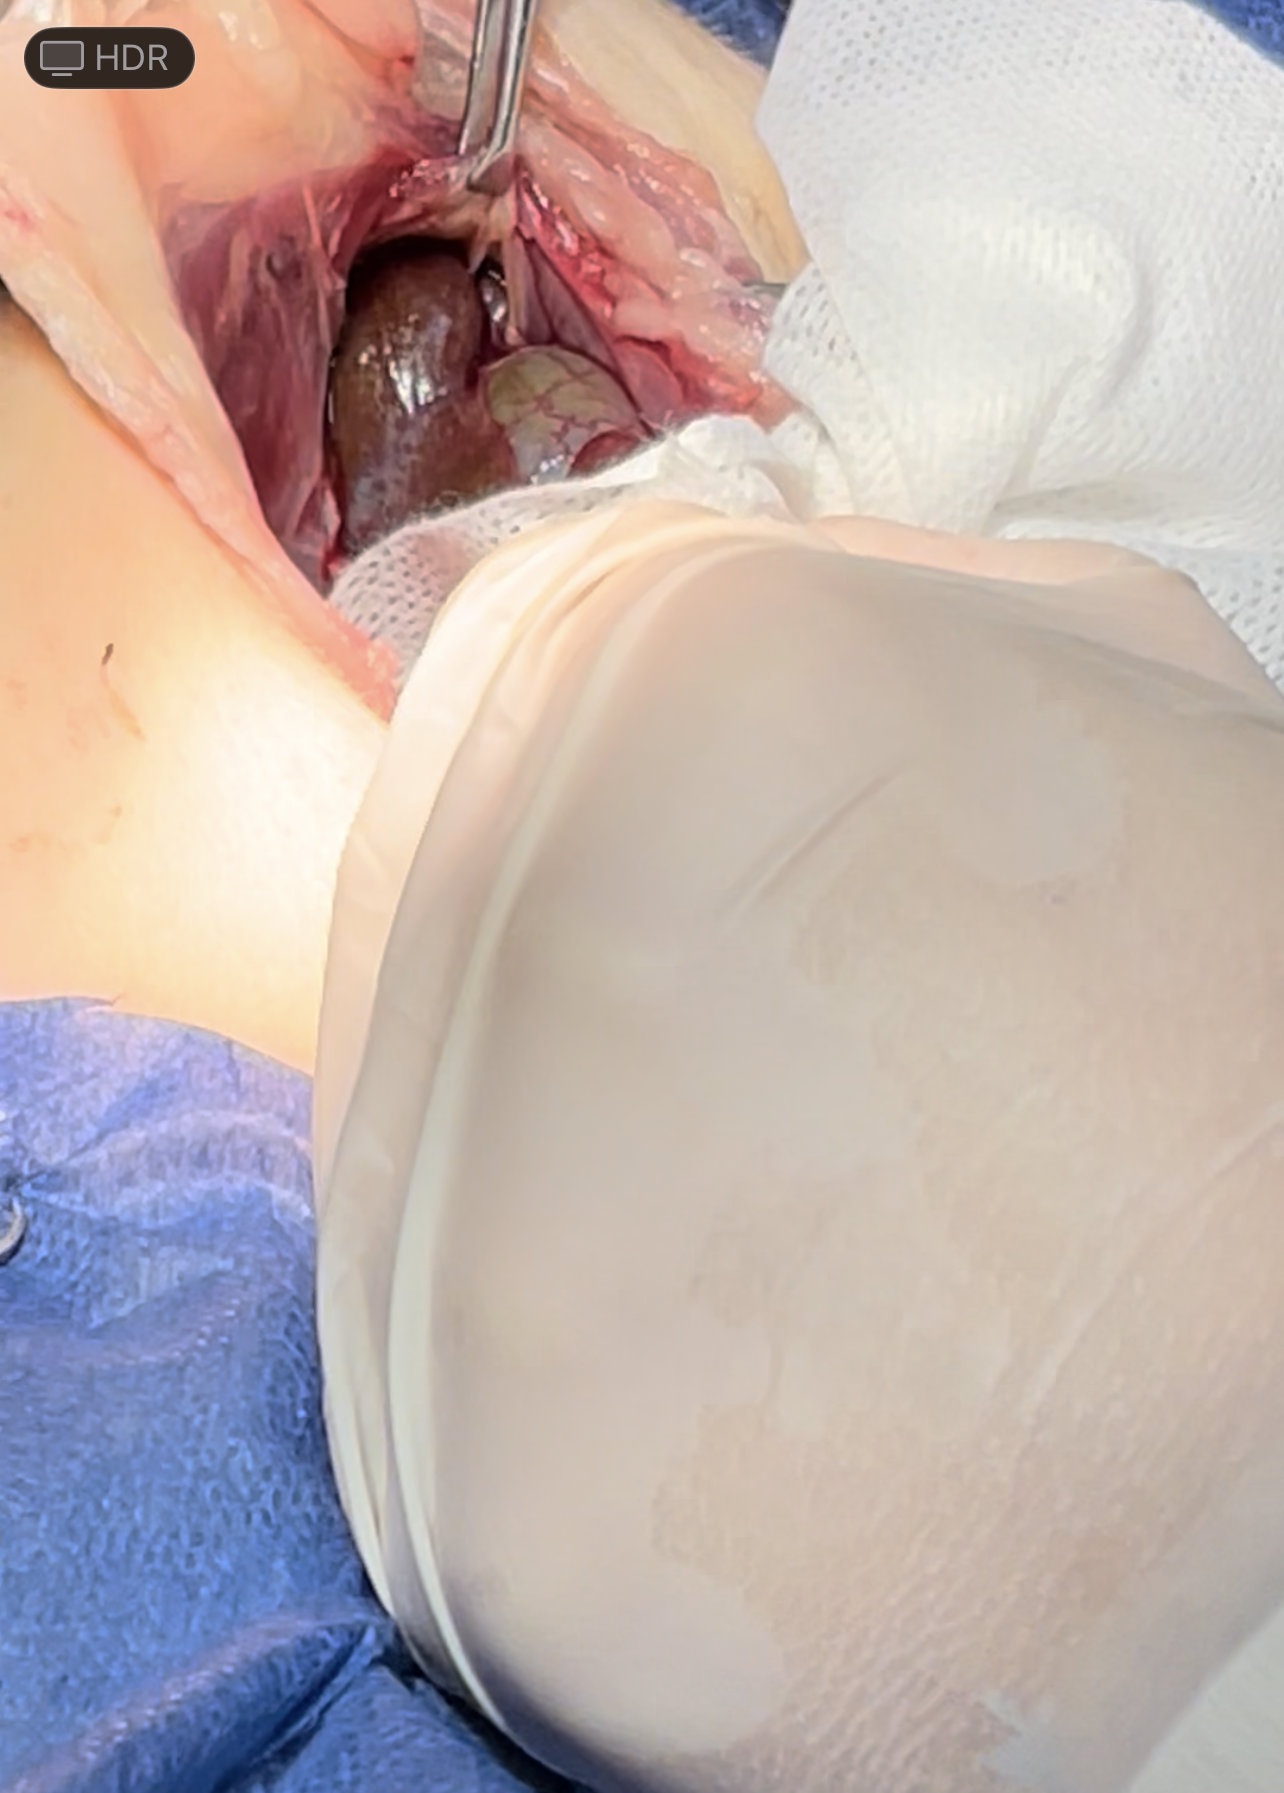

intestines & Liver lobe passing through a narrow hole after being healed over

Dissection of the intraabdominal adhesive part of the live

Widening the herniation to allow organ exteriorization